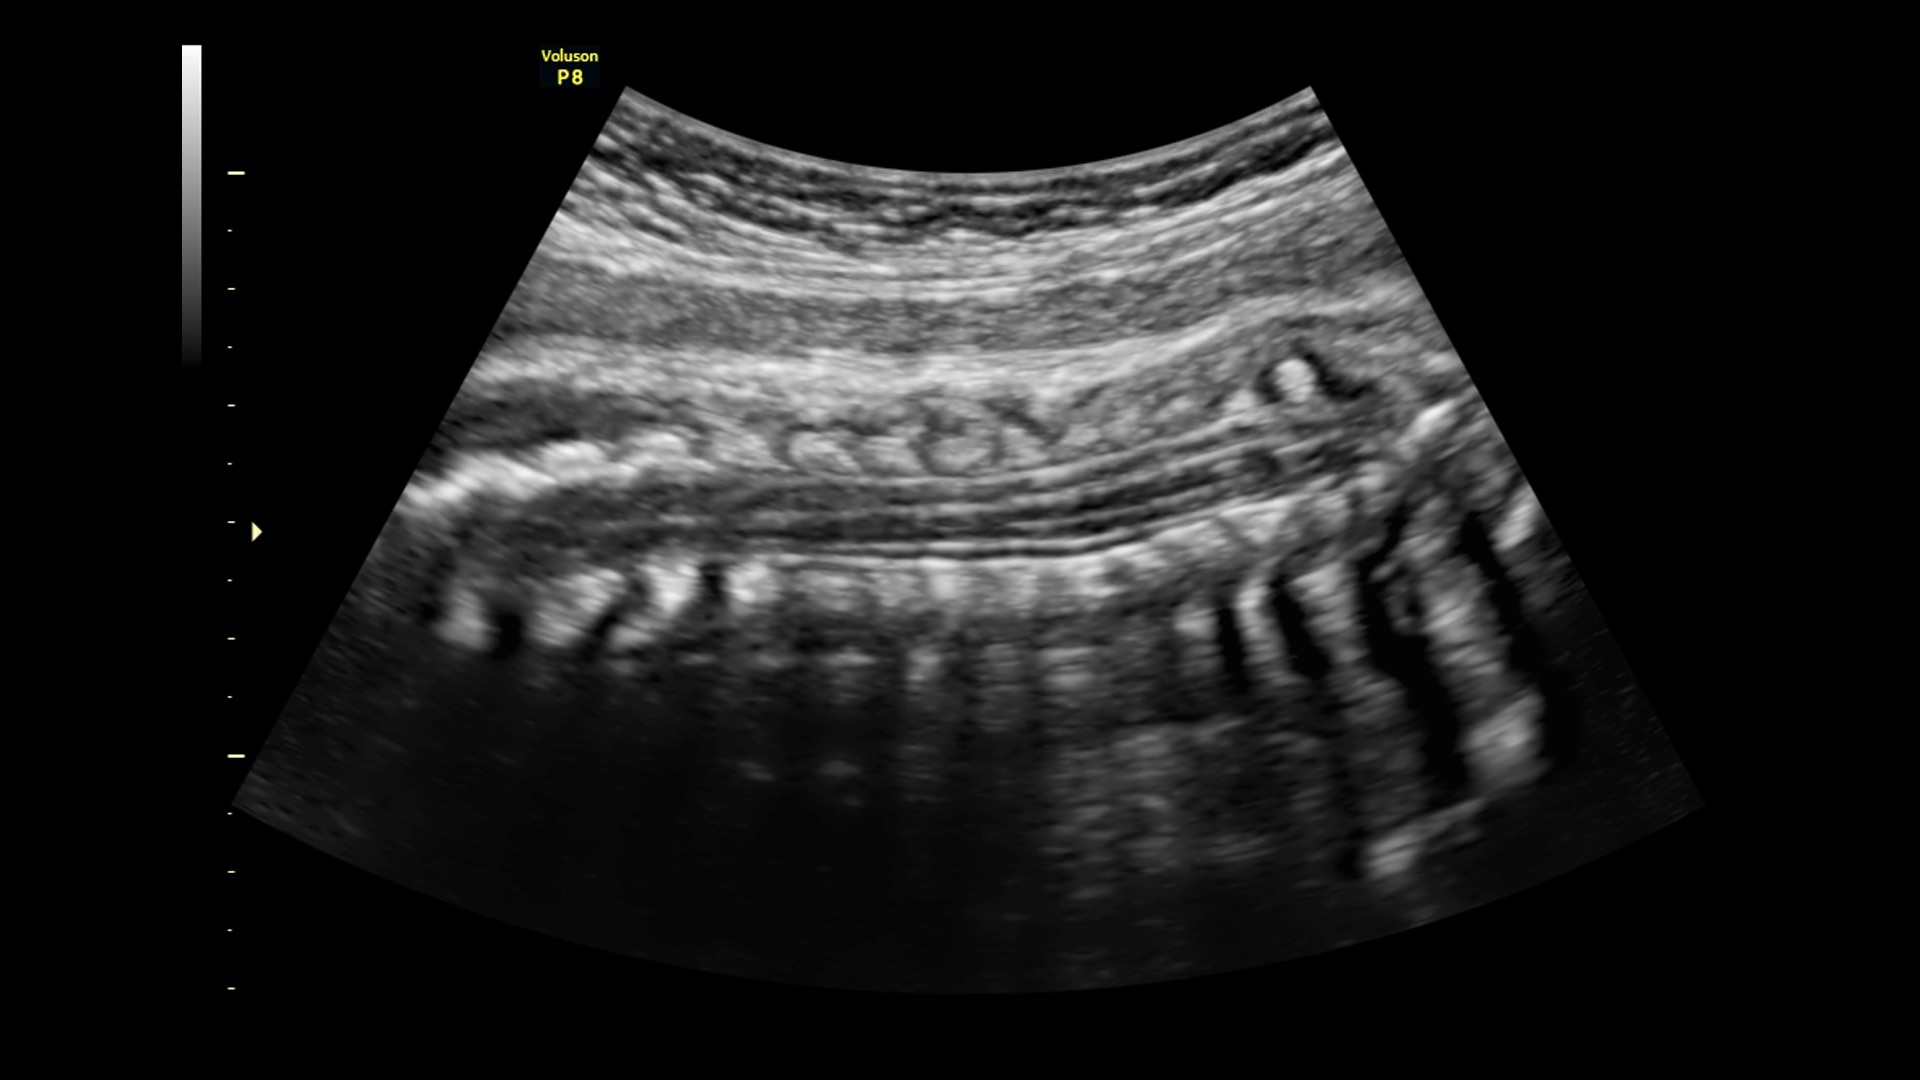

Simply place the probe to get the information you need. Built on Voluson Core Architecture, the P8 delivers excellent imaging across all types of patients and exams.

Enhance productivity and decrease exam complexity with Voluson’s Sono-Automation technologies. By automating functionality you can achieve greater consistency across exams and users.